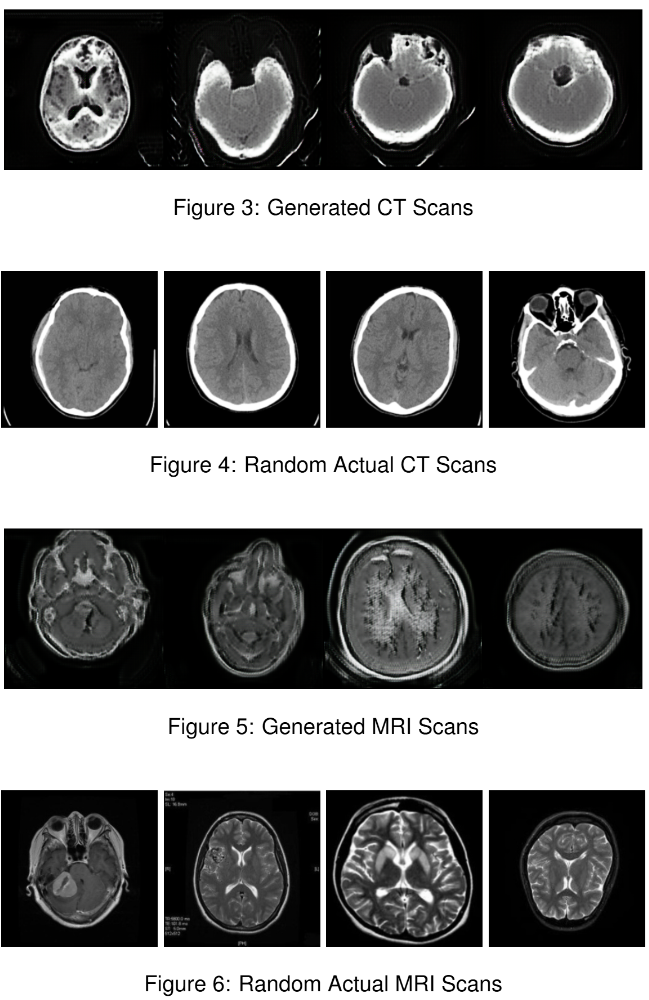

This project applies a CycleGAN-based architecture to translate CT scans into MRI images and vice versa. The model learns domain-specific features from each modality and performs unpaired image-to-image translation using cycle consistency. This enables synthetic generation of one modality from the other without requiring aligned datasets.

The system uses two generator-discriminator pairs trained adversarially. Cycle consistency ensures that an image translated from CT to MRI and back remains faithful to the original. This method allows the model to retain anatomical structure while adapting texture, brightness, and contrast between domains.

CycleGAN CT to MRI example